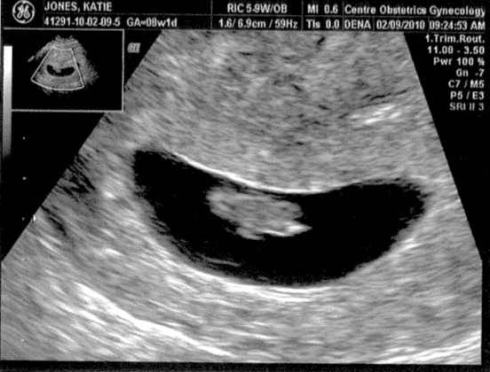

The little cahkah in the womb was measuring 1.3 cm at 7.5 weeks and the heart rate was 154. A week later, during our check up today, the cahkah was already at 2.1 cm. The doctor reminded us that second children are usually larger, and I noticed Katie cringe a little (bless her heart).

Here are a couple of early ultrasound images from last week.